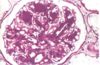

What antibody associated injury is pictured?

The image displays a linear pattern consistent with Anti-GBM Nephritis

Describe anti-GBM Nephritis

Fixed intrinsic normal antigens in the GBM are targeted by antibodies inducing a diffuse, linear, immunofluorescent pattern

The antibodies also cross react with other BM’s in the body, namely those in the alveoli. This is called Good Pasture’s Syndrome